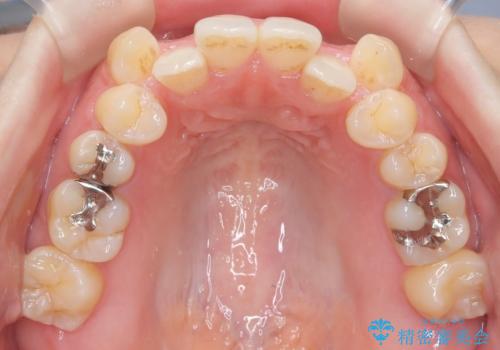

- 前歯のガタガタや八重歯の位置の乱れが気になっていた患者様に対して、ワイヤー矯正を行いました。矯正の過程で、スペースを確保するために上下左右の小臼歯を抜歯し、歯全体のバランスと機能性を考慮しながら理想的な歯列に仕上げました。

治療後は、前歯の位置や噛み合わせが整い、見た目も機能面も大きく改善されました。きれいな歯並びを得ることができ、患者様にも非常に満足していただけました。

抜歯によって確保したスペースを活用し、効率的に歯列を整えました。前歯のガタガタと八重歯が解消され、自然で美しい仕上がりを実現しました。